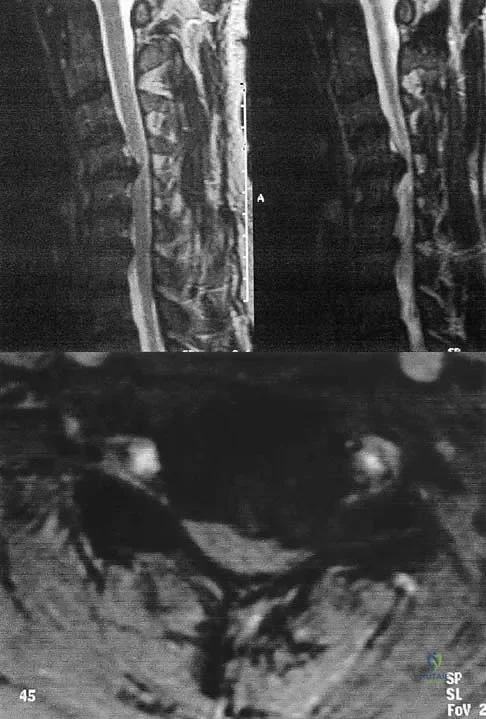

A patient who has had neck pain radiating down the arm for the past 4 weeks reports that the pain was excruciating during the first week. Management consisting of anti-inflammatory drugs and physical therapy has decreased the neck and arm symptoms from 10/10 to 3/10. He remains neurologically intact. MRI and CT scans are shown in Figures 5a and 5b. The best course of action should be

Explanation

A patient who has had neck pain radiating down the arm for the past 4 weeks reports that the pain was excruciating during the first week. Management consisting of anti-inflammatory drugs and physical therapy has decreased the neck and arm symptoms from 10/10 to 3/10. He remains neurologically intact. MRI and CT scans are shown in Figures 5a and 5b. The best course of action should be

Explanation